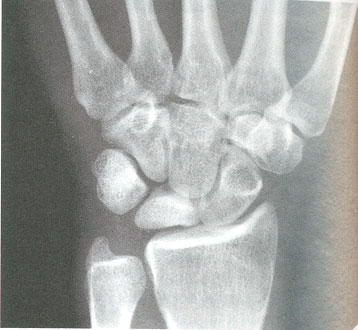

Figura 4: semilunar con esclerosis radiológica y pérdida de altura. Cúbito minus

Junto con los síntomas y la exploración física, es necesario realizar pruebas de imagen radiológicas. En la radiografía simple se pueden observar cambios en la densidad ósea del semilunar y las variantes morfológicas óseas (figura 4).

II: esclerosis radiológica con morfología normal (figura 6).

Figura 6 estadio II de la enfermedad de Kienböck